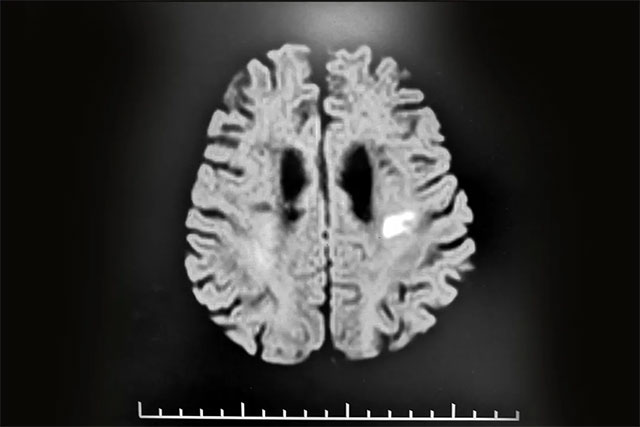

張靜波主任還接診了這樣一位腦;颊撸航衲7月初,68歲的程先生(化名),第一次患腦血管疾病,并以腦梗死形式發(fā)病,根據(jù)其頭部CT影像結(jié)果所示,其腦梗病灶并不是很大,但患者入院不久后就出現(xiàn)了一些精神障礙,表現(xiàn)為癡呆、答非所問,自言自語,記憶力減退,有時罵人,甚至有暴力的行為,這讓家人不知所措。

▲ 患者頭部CT所示:其腦梗病灶并不嚴(yán)重

對此,張靜波主任解說,一般正常情況,只有當(dāng)患者一次出現(xiàn)大面積腦梗,或其腦組織損害一次性超過80ml以上,才可能出現(xiàn)癡呆等表現(xiàn)。但患者程先生其腦梗病灶面積實(shí)際并不是很大,這就無法解釋他出現(xiàn)癡呆、罵人及記憶力減退等精神癥狀。